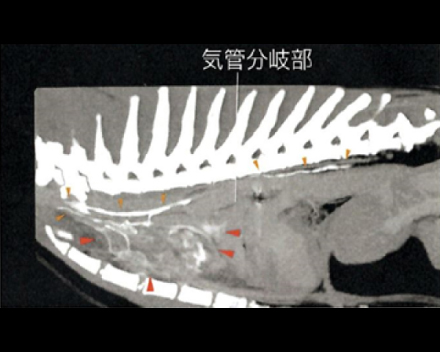

CT検査にて気管の圧迫を確認

内視鏡の位置をCアームで確認し正確に場所の把握が可能

2.8mmと5mmの内視鏡を用いて気管と食道両方の観察・生検が同時に実施可能